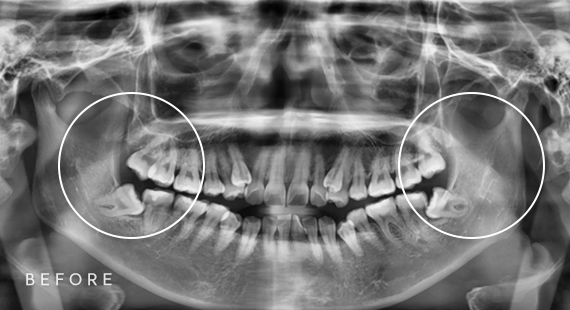

사랑니 발치